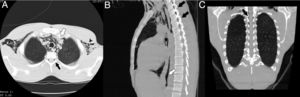

Ante la clínica y la imagen radiológica sugestiva de neumomediastino, se realizó tomografía computarizada (TC) donde se apreciaba neumomediastino que disecaba tráquea, bronquios principales, esófago, vena cava y espacio prevascular, hasta diafragma, sin datos de neumotórax u otra lesión. A nivel raquídeo se objetivó de forma casual gas desde las vértebras cervicales hasta las últimas vértebras torácicas (fig. 1).

La radiografía convencional es de elección ante la sospecha de neumomediastino. La imagen tomográfica puede resultar de utilidad para observar alteraciones asociadas, como el neumorraquis.